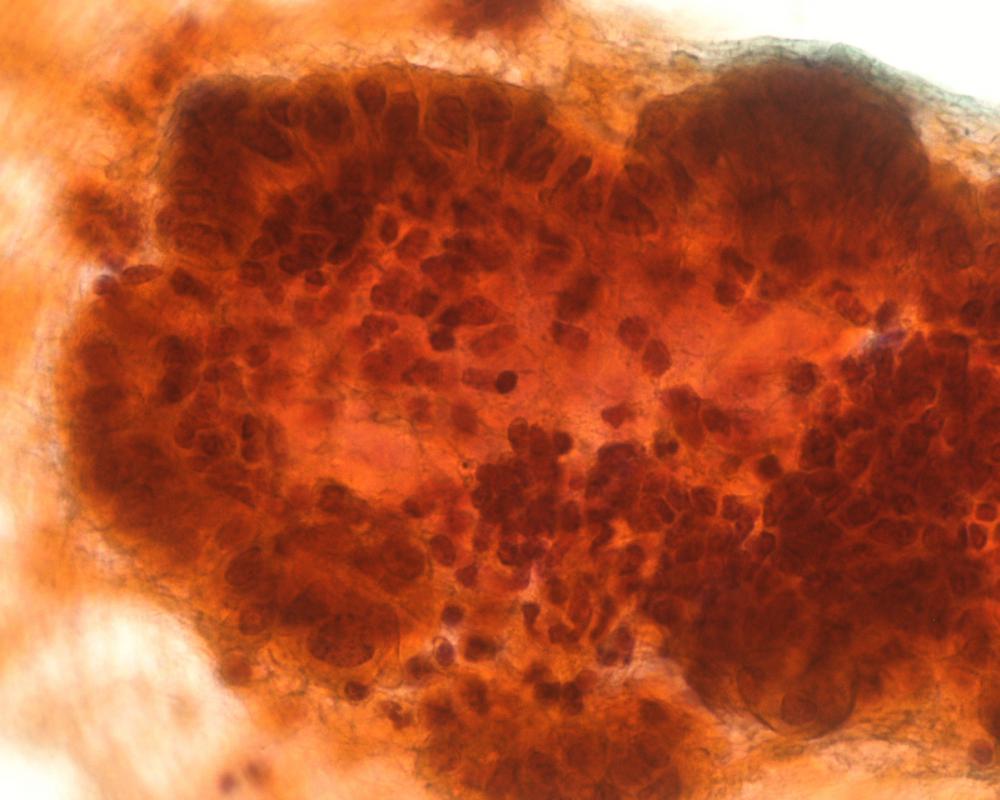

第34回日本臨床細胞学会九州連合会学会(長崎)スライドカンファレンス症例3

種別:泌尿器

出題:社会医療法人白十字会白十字病院 臨床検査科 大谷 博 先生

| 年齢 | 83歳 | 性別 | 男性 |

| 採取部位 | 左上部尿路 | 採取方法 | 左分腎尿 |

| 検体処理法 | LBC法(サイトリッチレッド, BD) |

既往歴:特記すべきことなし

現病歴:3か月前より肉眼的血尿が出現した。膀胱鏡にて膀胱後壁に径6 mmの単発性乳頭状腫瘍がみられたが,自然尿細胞診は陰性と診断された。CTにて左水腎症があり,下部尿管腫瘍が疑われたため左分腎尿が採取された。

| 正解 | 3.低異型度尿路上皮癌 |

| 1.尿路結石症 | 7件 | (7.2%) | |

| 2.内反性尿路上皮乳頭腫 | 40件 | (41.2%) | |

| 3.低異型度尿路上皮癌 | 39件 | (40.2%) | |

| 4.高異型度尿路上皮癌 | 1件 | (1.0%) | |

| 5.微小乳頭型浸潤性尿路上皮癌 | 10件 | (10.3%) | |

| 投票総数 | 97件 | (100%) |